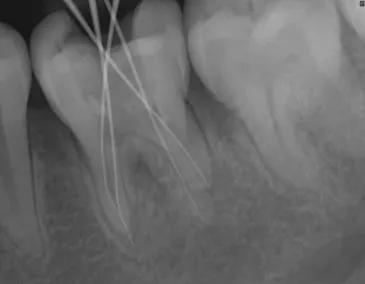

由于缺乏充分的侧支循环,牙髓一旦发炎,不能自行消除,必须摘除牙髓才能缓解症状,并且需要去除牙髓腔内的感染,再用生物相容性材料充填密封根管,杜绝再感染,临床上应用最广的方法是根管治疗术。通过及时有效的治疗,患牙一般都可以保存。但若治疗不及时,感染会进一步扩散,引起根尖周的炎症,甚至最终导致牙器官的丧失。